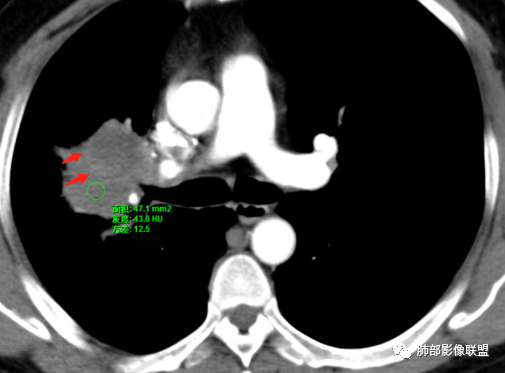

了:中年男性,右肺门肿块影,浅分叶,周围晕征,边缘清楚,小叶间隔增厚,树芽征,支气管截断,不均匀强化,内可见低密度坏死,纵隔淋巴结肿大,综合考虑肺部肿瘤并阻塞性肺炎

一切∮随缘:右肺门肿块影形态不规则,边缘毛糙,右肺上叶支气管堵塞,病变跨叶生长,远端血管束增粗,周围散在多发结节,部分位于胸膜下,平扫密度尚均匀,增强后不均匀强化,呈中度强化,坏死区无强化,纵隔淋巴结肿大。临床无感染症状,考虑恶性,鳞癌,腺癌,鉴别慢性脓肿。

那个人:中年男性,右肺肿块影,支气管截断,截断口非圆盾,病灶膨隆分叶,坏死,强化。病灶内血管破坏。病灶远端树芽及小结节影,考虑恶性,鉴别结核

周太狼:中年男性,吸烟史,陈旧结核史,呼吸道症状未提及,抗感染治疗无效。影像见右上肺门区软组织肿块影,浅分叶、毛刺,支气管似有截断,其内密度不均匀,不均匀强化,内可见低密度坏死区,病壮周围见斑片、结节影。纵隔内淋巴结稍肿大,首先考虑恶性,肺部肿瘤并阻塞性肺炎,肺鳞癌可能,鉴别结核。

弹指之间:中年男性,结核史、吸烟;右肺门肿块,特点:右肺上叶尖、前段支气管狭窄、部分阻塞(肿块大、支气管狭窄闭塞相对轻),肿块内血管部分残留(生长速度快,浸润>破坏),周围见渗出、炎症,部分实变;内见坏死、位于边缘区域;纵隔淋巴结肿大;考虑恶性,1.非支气管粘膜起源首先考虑,淋巴瘤?(但坏死相对多了);2.鳞癌(支气管阻塞轻);3.小细胞待排。

Coke with ice:病变整体收缩平直,毛刺较软,支气管壁增厚。支气管鼠尾状狭窄,于病灶以远可见显示。支气管粘液栓。相邻支气管血管推移明显,磨玻璃边缘模糊,多灶坏死边缘清晰,一部分血管自然穿行,猜个炎性病变。

这个比较大的坏死灶,边缘清晰,看似符合鳞癌坏死。仔细看看这个坏死边界,是血管阻挡引起的边界清晰。其他的病灶内低密度是柱形粘液栓。实性部分强化有轻度延迟强化。病变背景是双上肺的小叶中心结节。病变区的支气管壁是厚的。

妞妞:右肺门区病灶,边缘有GGO,模糊,远端树芽,支气管受阻,有圆钝感,病灶坏死,边缘清楚,实性成分有强化,不像鳞癌强化,首先考虑结核,鳞癌待排,建议支气管镜

良孑:右肺门肿块,有平直,u型凹陷及尖角征,远端可见散发树芽征,有支气管截断,肿块内坏死边界清,似可见围绕坏死的环状强化,综合分析首选炎性病变,TB可能,冇吸烟史,良恶性征象都有鳞癌要鉴别,